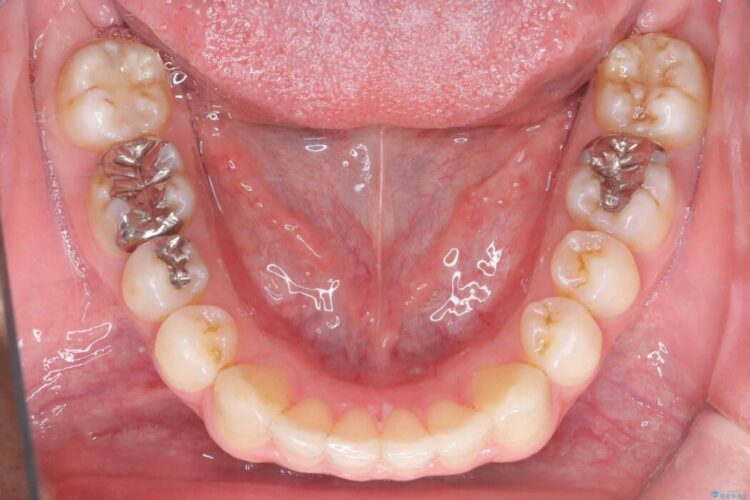

正中離開・叢生のほかに、上下の奥歯が全く咬み合わないシザーズバイトの状態も認められました。

歯の隙間とデコボコ、シザーズバイトも改善され、咬み合わせや見た目が整い、患者様にも大変ご満足いただけました。